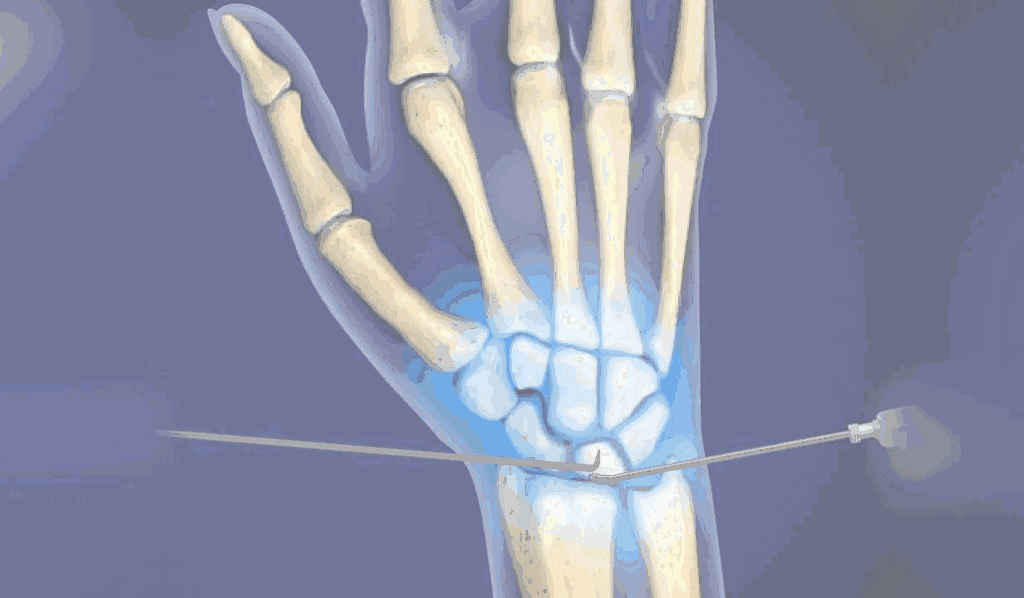

The young, male patient had the fracture of Rt scaphoid/ due to falling on an outstretched hand. The scaphoid fracture was treated, with the plaster cast for 1 ½ month elsewhere. Fracture of Rt Scaphoid was not united. This condition is called, the scaphoid non-union. It was treated with open reduction, and the iliac crest, bone grafting, and K wire stabilization.

During Surgery